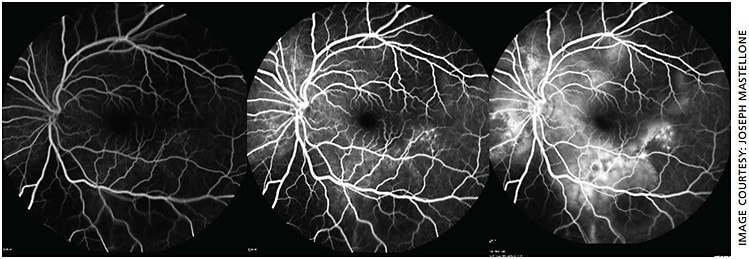

- OS fluorescein angiography: Initial blocking defect of normal choroidal circulation inferiorly due to sub-retinal fluid, followed by early multiple stippled-pinpoint hyperfluorescence temporal to the macula with late pooling of fluorescein dye (Figure 3)

Pathologically, the sympathizing eye demonstrates diffuse uveal tract (especially choroidal) thickening, sub-retinal fluid and/or exudative retinal detachment and Dalen-Fuchs nodules. Inflammatory responses are likely responsible for the uveal tract thinning, which recruits immunologic cells that accumulate underneath the retina and may cause detachment.

Dalen-Fuchs nodules are found between retinal pigment epithelium and Bruch’s membrane in approximately 33% of SO cases. They consist of epithelioid cells containing phagocytosed uveal pigment.6 Because SO closely resembles VKH, differentiating them is clinically relevant. SO spares the choriocapillaris, lacks systemic (neurological, cutaneous) symptoms and has a history of penetrating trauma.4